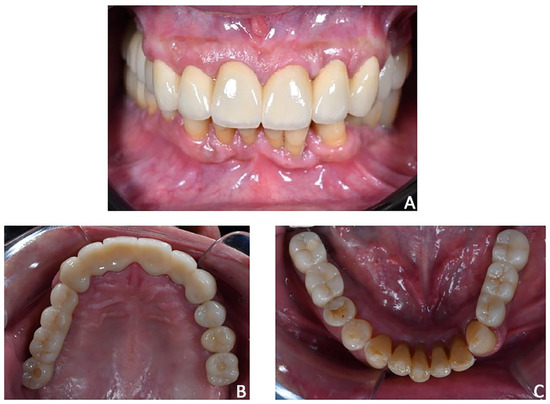

Figure 20. Case 3. The case was finalized by replicating the information functional characteristics of the provisional crowns in the final definitive prosthesis. (A) Intra-oral frontal view; (B) occlusal upper view; (C) occlusal lower view.

Prosthetic finalization. After orthodontic treatment, posterior rehabilitation was completed by replacing the temporary crowns with monolithic zirconia crowns screwed on implants (Figure 19A). In the same appointment, provisional crowns were applied in the upper anterior segment from 1.3 to 23 and kept for one month (Figure 19B). After the final aesthetic and functional analysis wards, the case was finalized by replicating the information and functional characteristics of the provisional crowns in the final definitive prosthesis (Figure 20). The upper fixed prosthesis was zirconia-ceramic, stratified in the vestibular (not functional) area.